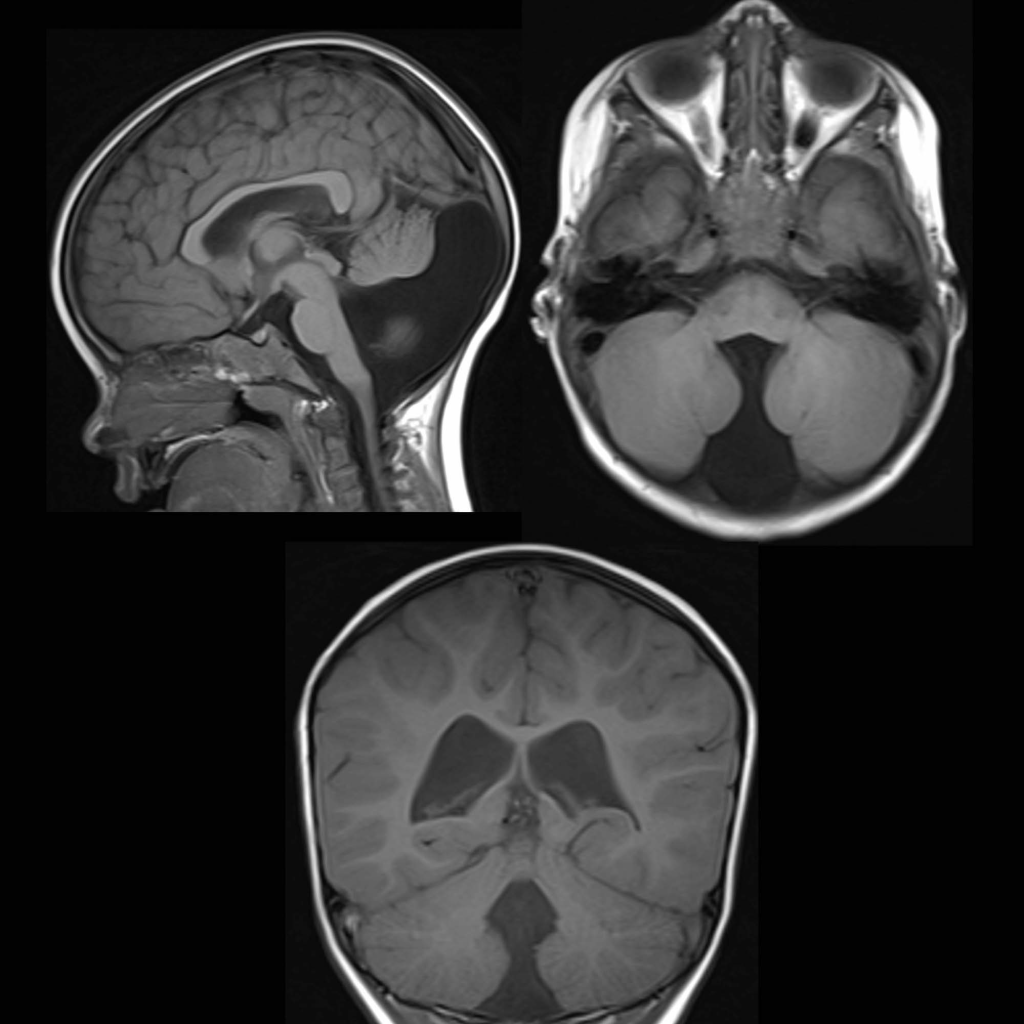

Dandy-Walker malformation (DWM) is a congenital brain abnormality arising from improper embryonic development of the cerebellum and 4th ventricle, characterized by an underdeveloped cerebellar vermis, a cystic, enlarged 4th ventricle, and an enlarged posterior fossa. These structural changes frequently lead to hydrocephalus, a buildup of cerebrospinal fluid that increases intracranial pressure and causes head swelling, which can result in significant neurological impairment.

Dandy-Walker malformation is diagnosed through imaging techniques, primarily ultrasound, CT scans, and MRI.